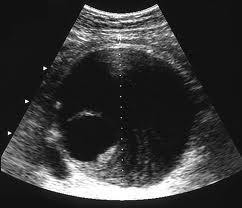

Abnormal dilatation of a vessel wall, more than 50% of its normal diameter is considered as aneurysm. Abdominal Aortic Aneurysm (AAA) is abnormal dilatation of abdominal aorta, more than 3cm in diameter. Commonest area involved is infra-renal aorta. (Figure 3)

Figure 3. Illustrating common site of  Abdominal Aortic Aneurysm